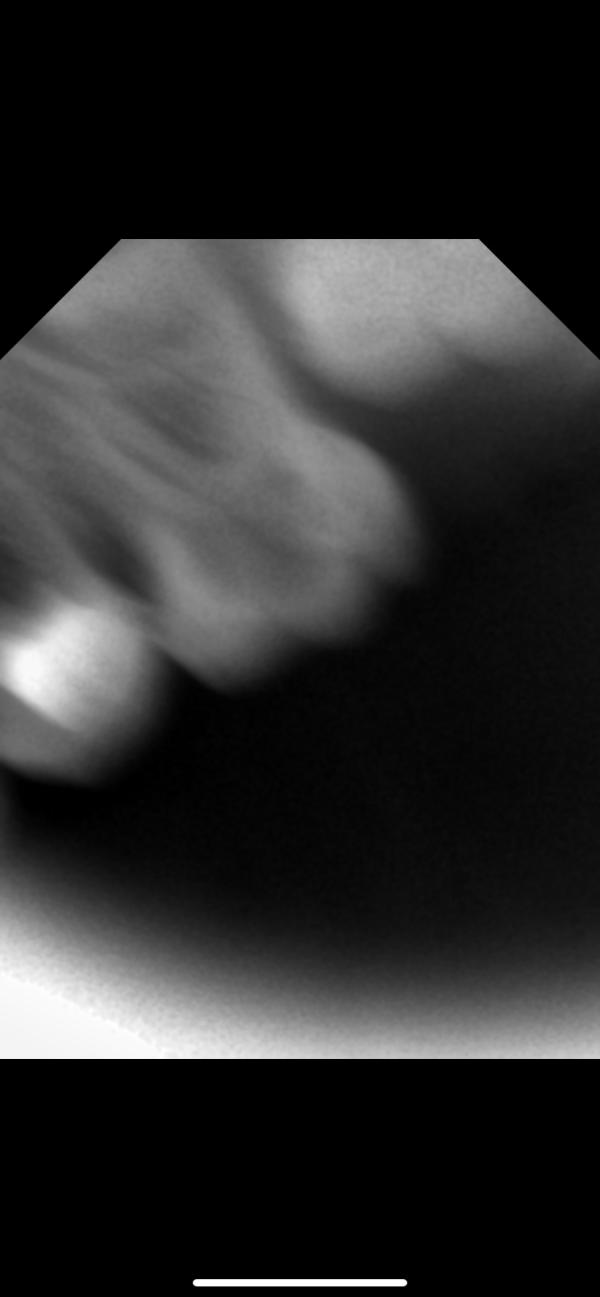

Левую единицу удалять 100%. Остальные хорошо бы переделать снимки в другой проекции, не совсем понятно